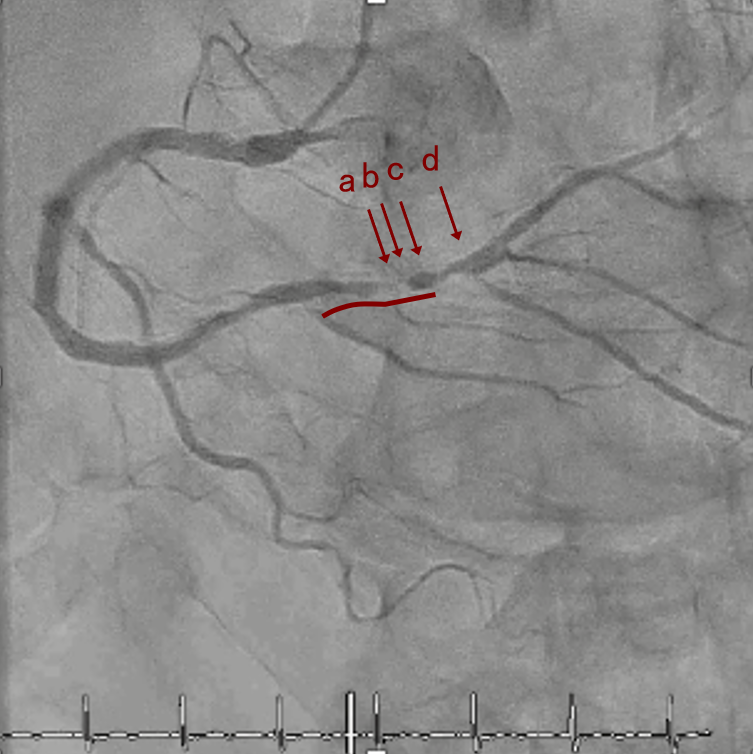

OAS low speedによる引きを赤線の区間行う方針とした。

OAS low3回 造影上の切削区間の確認

そのためcでIVUSマーキングを行い、その点より引きで赤線のpinpoint OAS high speedを行い、dに関してはinjury回避のためにOASを当てない方針とした。

しっかりIVUSマーキングした安全な位置から、造影で確認してOASの引きを繰り返す

IVUS マーキング

OAS開始点